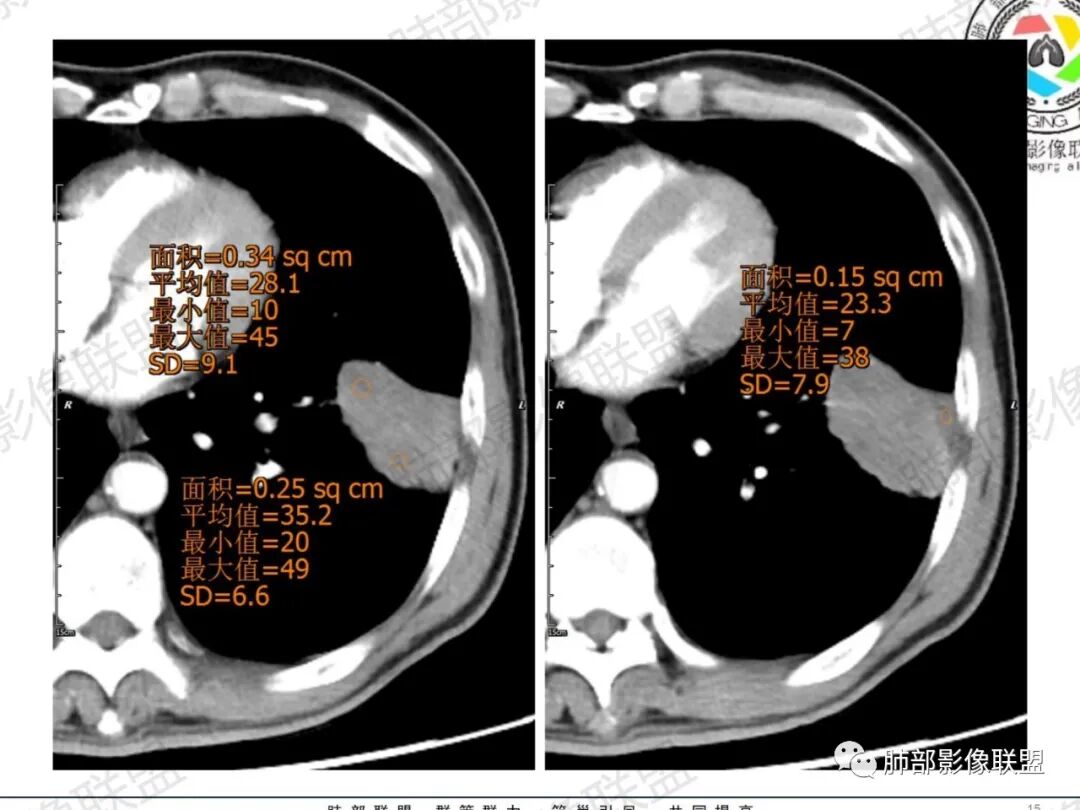

一切∮随缘:左肺下叶不规则肿块,边缘光滑,平直,局部彭隆,分叶,近端支气管堵塞,远端与胸膜相贴,平扫密度尚均匀,增强后不均匀强化,内部可见低密度坏死,胸膜下多发肺气肿,伴双肺散在光滑小结节,实验室肿瘤标志物高,考虑恶性:神经内分泌癌(大细胞),腺癌,鳞癌。

琦遇:恶性没有问题,肺气肿底子、病灶分叶、少许毛刺、叶间胸膜凹陷、部分边缘可见清晰的GGO、胸膜牵拉凹陷、局部胸水、近端支气管截断、部分支气管被推移、占位效应明显、强化特点为不均匀强化、内部有少许沼泽样低强化区,强化部分轻中强化为主、余肺可见转移性结节、左肺上叶似为囊腔型腺癌一枚,肿瘤标志物提示非小、神经内分泌,综合分析考虑大神泌、腺癌、腺鳞癌、鳞癌  同时左肺上叶囊腔型腺癌  肺转移

飞鹰行动:中年人,男性,胸疼入院,左肺下叶占位,张力较高,边界可见分叶,局部可见明显收缩性改变,增强病灶内部有延迟强化表现,考虑恶性病变,大细胞癌伴肺内转移或者囊腔样腺癌伴转移。

蕊:中老年男性,吸烟史,肺气肿背景,左肺上叶类圆形肿块影,边界清晰,边缘凹凸不平,有分叶,支气管进入阻断,临近胸膜栽赃,整体病灶膨隆,局部周围可以清晰ggo,临近叶间裂内凹,轻度强化,并可见多个低密度区,坏死可能,界线不清;肺内多结节,边缘光滑,考虑恶性伴转移,鳞癌、腺癌

傅昌瑜:中老年男性,肺气肿背景,右胸背疼痛1周。CEA、NSE、CYFRA—211升高。左上肺混合磨玻璃结节,内见较多空泡和扩张支气管。左下肺胸膜下肿块,边缘较光滑,深分叶,似有血管进入,与支气管关系不清,内见不均匀强化,见沼泽地样坏死,有胸膜栽赃。另两肺多发圆形小结节。考虑恶性并肺内转移,多原发可能性大,左上肺腺癌,左下肺病理难以判断,小细胞癌?鳞癌?

小锁:中老年男性,肺气肿背景,右胸背疼痛1周。CEA、NSE、CYFRA—211升高。左上肺混合磨玻璃结节,边界清楚,内见较多空泡。左下肺肿块,边缘清楚,深分叶,有血管和支气管进入,胸膜凹陷。另两肺多发圆形小结节。考虑双发原位癌,左上肺腺癌,左下肺大神泌或腺鳞癌可能,肺内转移。

蓝天白云:中年男性,肺气肿背景,左肺下叶肿块,边缘膨隆,有分叶,内有湖泊样坏死,有轻中度强化,局部胸膜栽赃,收缩力不强,周围见肺气肿征象。左肺上叶混合磨玻璃影,边界清楚,考虑都是恶性,左上肺iac,左下肺腺鳞癌,或大细胞肺癌可能。两肺多发结节,考虑转移

毛勤香:老年男性,肺气肿背景,左肺下叶肿块,分叶,边缘光滑,土豆块样,细支气管闭塞,增强轻度不均匀强化,似有坏死,左肺另见多发结节,淋巴结未见明显肿大,恶性确定,吸烟史,鳞癌破坏力强,侵袭力差,多原发的一般很少多于3个,故排后,首先考虑神经内分泌癌,局部血管穿行,鉴别淋巴瘤

周太狼:中年男性,吸烟、高血压史,肿瘤指标升高,肺气肿背景下,左肺下叶肿块影,分叶、膨隆、未跨叶裂,支气管截断,不均匀强化。另双肺多发结节及磨玻璃影,左肺上叶混合磨玻璃,内可见多发空泡影。整体考虑恶性,肺癌伴肺内转移,左下肺鳞癌?神经内分泌癌?左肺上叶囊腔腺癌?

LCNEC最常见的影像特征包括:(1)肿块发生部位:周围型肺癌为主,少数发生于肺中央。(2)肿块大小及形态。因肿瘤细胞生长迅速常形成较大肿块,因此其体积一般较大,直径常在3~10cm范围内,病灶常为不规则形软组织肿块。(3)肿块边界。多数学者报道大多数肿块边界清晰,边缘呈分叶状,毛刺征及“胸膜凹陷征”少见,认为与该病对周围组织浸润较轻及较少产生纤维瘢痕组织牵拉有关联。(4)肿块密度、强化特点及代谢情况。据文献报道,该类肿瘤因体积较大CT上常见软组织肿块,且多数密度不均匀,内见囊变坏死区,增强后呈轻或中度不均匀强化(可见强化者占75.7%),认为其强化特点与其内部肉眼可见坏死灶和肿瘤较大直径有关。(5)伴随症状及远处转移。该病恶性程度高,侵袭性强,常侵犯邻近结构,如胸膜、心包、邻近骨质或纵隔内组织等,易出现纵隔淋巴结转移,部分发生肺内及远处转移,少数早期可出现广泛远处转移。